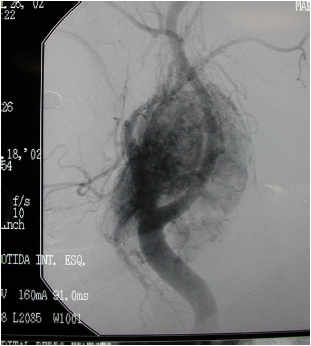

Paciente relata crescimento de tumoração na região cervical. Realizou o exame que evidenciou a lesão abaixo.

A hipótese diagnóstica é: